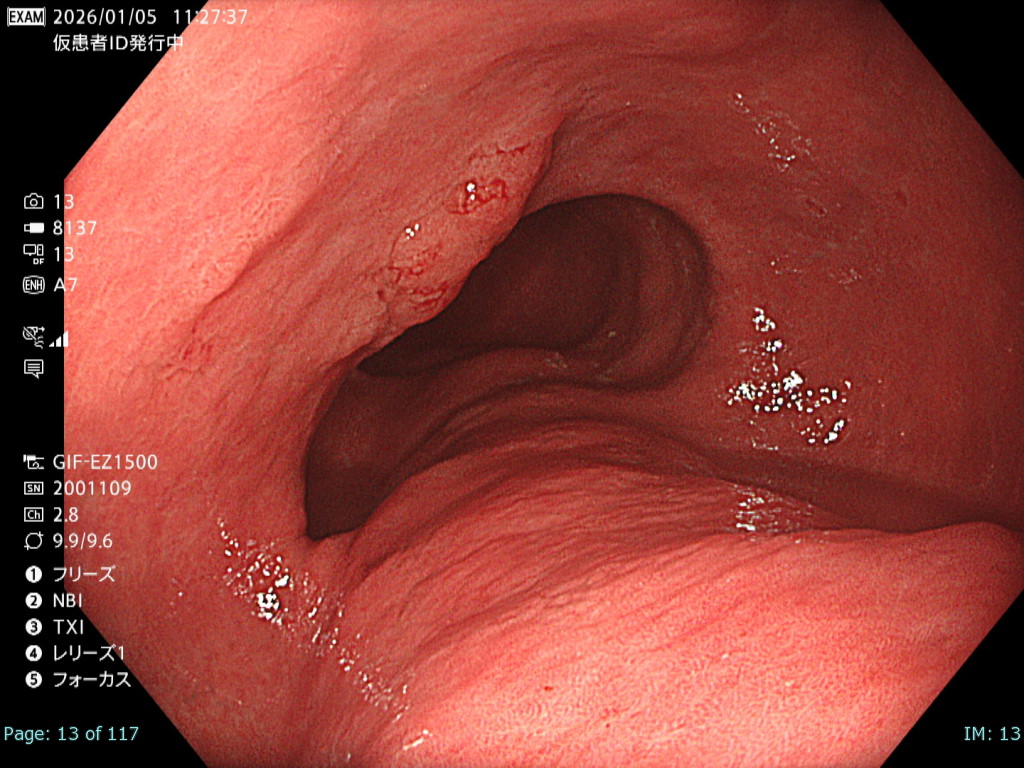

• 白色光観察②(中遠景)

強調設定:A7

図1

白色光非拡大観察では画面全体に良好なフォーカスが得られており、さらにBAI-MAC機能により深部まで十分な明るさが確保されている。そのため、2病変の性状および位置関係を正確に把握することが可能である。

• 白色光観察①(近景)

図2

本病変は易出血性であり、血液洗浄後に観察・撮影できる時間は極めて短かったが、表面構造および色調を損なうことなく病変が明瞭に描出されている。記録画像として再評価にも十分耐え得る内視鏡画像である。